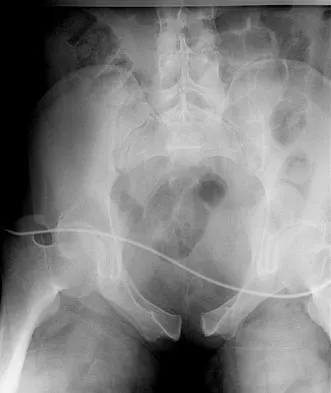

Which of the following findings is seen in the chest radiograph shown in Figure 13?

Orthopaedic surgeons are often responsible for interpreting radiographs of general examinations such as the chest radiograph shown. For accurate interpretation, it is important to systematically review all of the information available on the radiograph. Using this approach, the fracture of the left proximal humerus is readily recognized. Linear air soft-tissue density at the lung periphery would suggest a pneumothorax, but this finding is not shown on the radiograph. The upper thoracic spine is well aligned. The sternoclavicular and distal clavicles are normal.